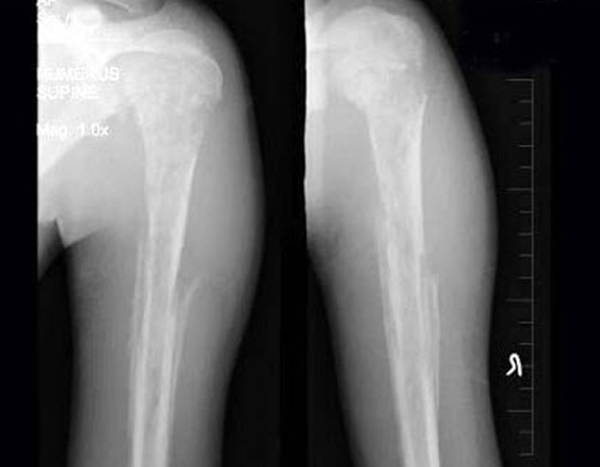

查瞅:厚皮性骨膜病的X线查瞅瞅来胫骨、腓骨、桡骨、尺骨等部位有增素性骨膜炎、充溢性骨膜增厚。

诊疗:依据皮肤及骨骼X线查瞅睹增素性骨膜炎、充溢性骨膜增厚的典范临床转变可作出诊疗。